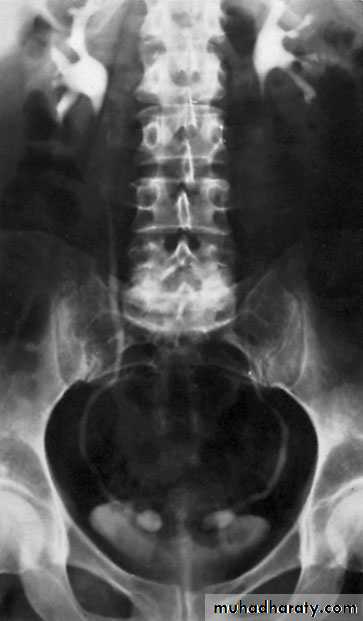

Ureteropelvic Junction (UPJ)(PUJ) Obstruction (stenosis)

The most common cause of significant dilation of the collecting system in the fetal kidney

Boys > Girls

Left-sided lesions predominate

15% bilateral

DIAGNOSIS

U/S: hydronephrosis

IVU: diagnostic , hydronephrosis with

fixed stenotic segment or complete

obstruction

CT scan: hydronephrosis that ends

abruptly